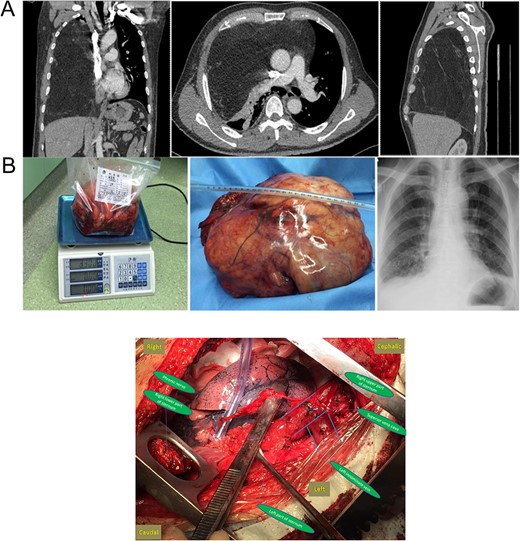

(A) Preoperative chest CT and (B) gross specimen and postoperative chest X-ray. Central Picture: “⊣ shape” incision and intraoperative surgical field after removing the giant mass.

Surgical exploration was performed first through a standard median sternotomy under general anesthesia. Dissection started from left phrenic nerve along the left innominate vein to superior vena cava. However, the giant tumor adhered severely to pericardium and the lower part of superior vena cava. Sternum transection plus a right fourth intercostal thoracotomy (‘⊣ shape incision’) was then added to guarantee a better exposure. Intraoperatively, a giant, well-capsulated yellow tumor without abundant blood supply was found, which also occupied the whole right thorax without invading the lung, chest wall, diaphragm and inferior vena cava. The main part of the tumor was smoothly removed from the right thorax after cutting off the mass along the pericardium, superior vena cava and pulmonary hilum. After careful dissection of adhesion, the rest of the tumor was gradually separated and successfully removed with partial pericardium (Central Picture). The atelectatic right lung obtained good reexpansion when both lungs were ventilated.